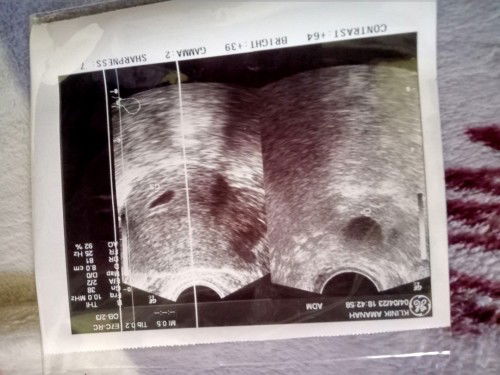

Membaca hasil usg

Mau tanya bun apakah ada yang bisa baca usg trans v ?itu brapa minggu ya mohon bantuannya🙏

hm.. emg bunda hpht nya kapan? hasil usg diatas tdk ada tulisan brp minggu nya. setau saya kalo baru terlihat kantungnya aja itu sekitar 5mingguan